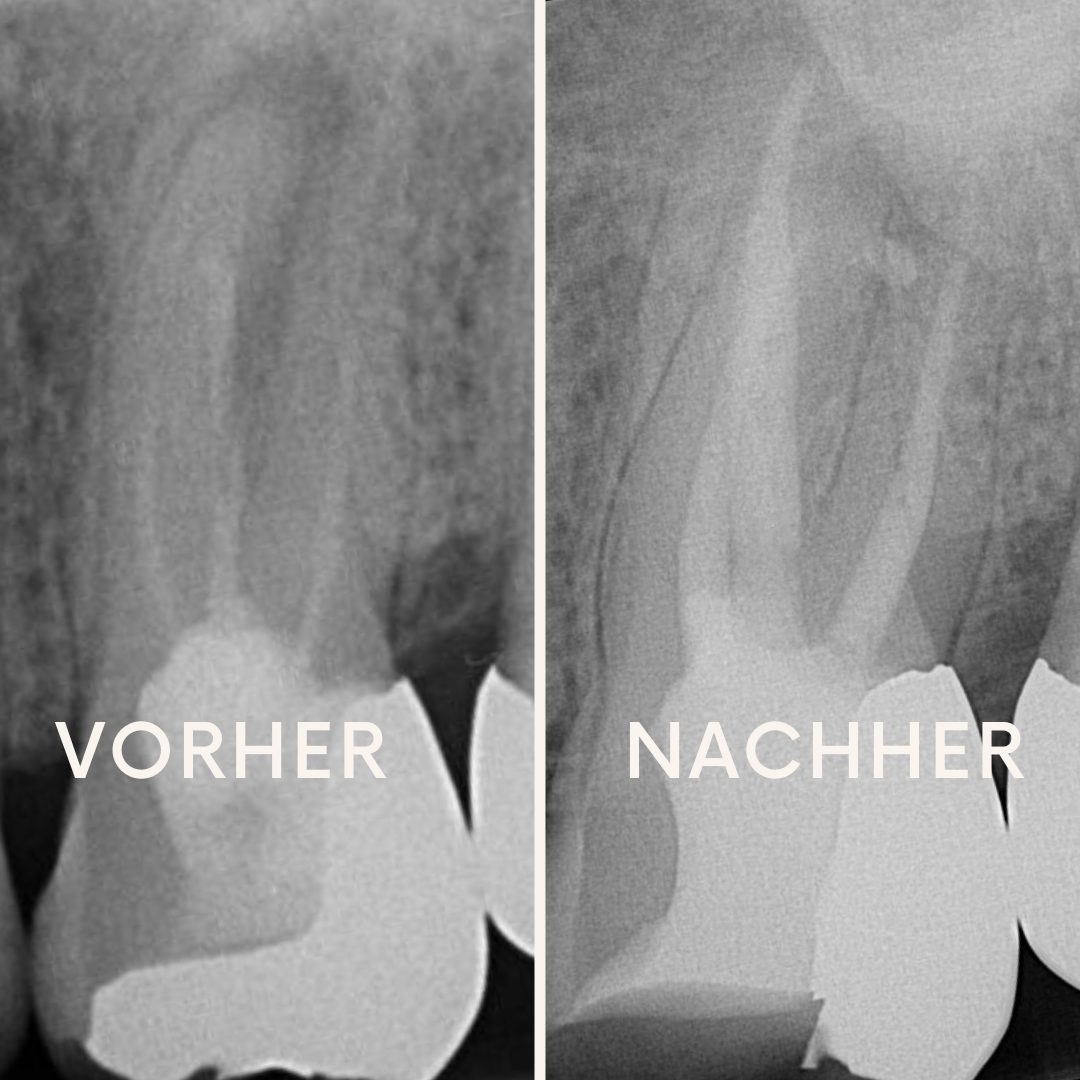

Fallbeispiele für Seitenkanäle und Schallaktivierung der Spülflüssigkeiten